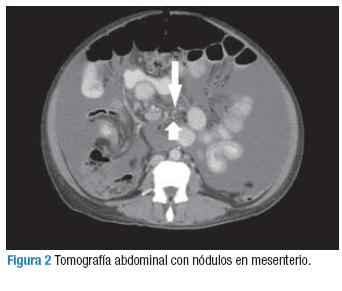

Paciente femenina de 43 años, sin antecedentes de importancia, procedente del área rural de la Orinoquía colombiana, quien consultó por cuadro clínico de 1 año de evolución consistente en aumento progresivo del perímetro abdominal acompañado de pérdida de 10 kg de peso, sin fiebre, sintomatología respiratoria o gastrointestinal asociada. Fue remitida inicialmente a consulta de ginecología con signos vitales normales y presencia de ascitis grado 2 sin otros hallazgos al examen físico. Por lo anterior, se realizó ecografía y tomografía de abdomen que evidenciaron ascitis abundante (Figura 1) y múltiples nódulos de tejidos blandos en mesenterio (Figura 2), se sospechó carcinomatosis peritoneal. El hemograma, las pruebas de función renal y hepática fueron normales.